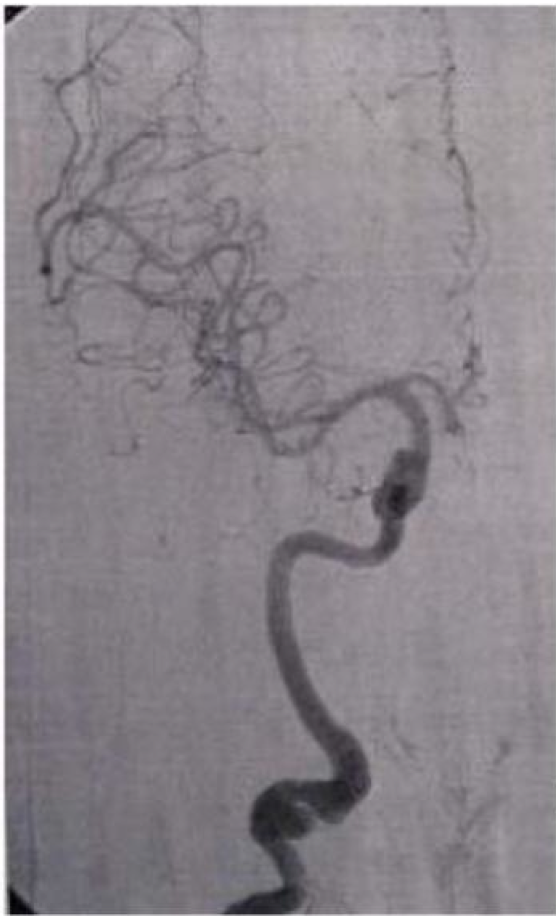

di bawah ini adalah gambar dari?

A. Fetal origin of the posterior cerebral artery

B. Moyamoya disease

C. Persistent acoustic artery

D. Persistent hypoglossal artery

E. Persistent Trigeminal Artery

A